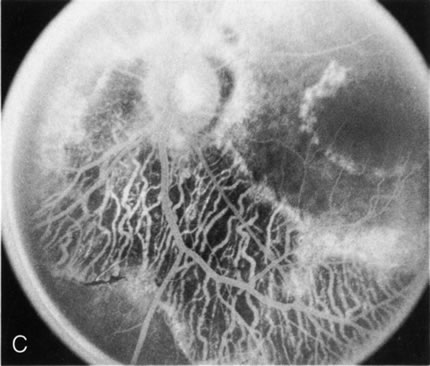

Generalized choroidal dystrophy is usually noted in middle-aged mildly symptomatic individuals who show a predominantly peripapillary or pericentral distribution of choroidal atrophy. Gradually, over the years these areas enlarge to eventually involve the entire retina. These changes are vividly seen on FA (Fig. 6).

Fig. 6. Generalized choroidal dystrophy. This 65-year-old woman gradually developed enlarging, progressive areas of choroidal atrophy over a 20-year period. When initially seen, the abnormalities were confined to the peripapillary and macular region (A,B). In a recent examination, the generalized choroidal atrophy is vividly demonstrated on angiography (C–F).